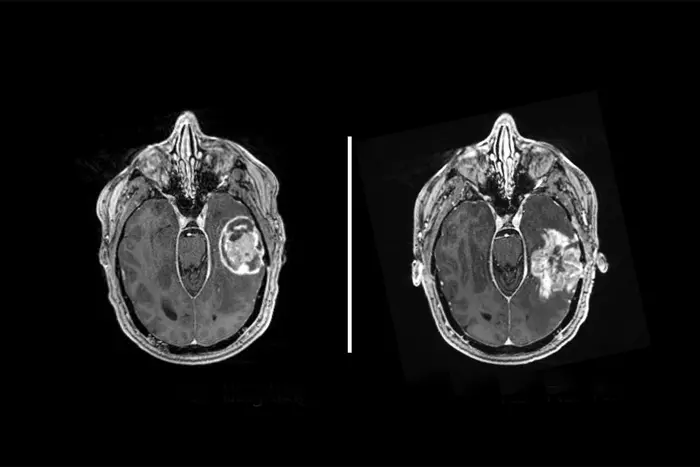

Selbst mit den modernsten Therapien überleben Patienten mit Glioblastomen – einem aggressiven Gehirntumor – nach der Diagnose in der Regel weniger als zwei Jahre. Versuche, diesen Krebs mit den neuesten Immuntherapien zu behandeln, waren bisher erfolglos, wahrscheinlich weil Glioblastomzellen nur wenige oder gar keine natürlichen Angriffsziele für das Immunsystem haben. In einer zellbasierten Studie haben Wissenschaftler der Washington University School of Medicine in St. Louis Glioblastomzellen dazu gebracht, Ziele des Immunsystems zu präsentieren, wodurch sie möglicherweise für Immunzellen sichtbar und für Immuntherapien anfällig werden. Die Strategie beinhaltet eine Kombination aus zwei Medikamenten, die beide bereits von der FDA zur Behandlung unterschiedlicher Krebsarten zugelassen sind. Die Studie ist online im Fachjournal Nature Genetics erschienen . https://www.nature.com/articles/s41588-024-01880-x